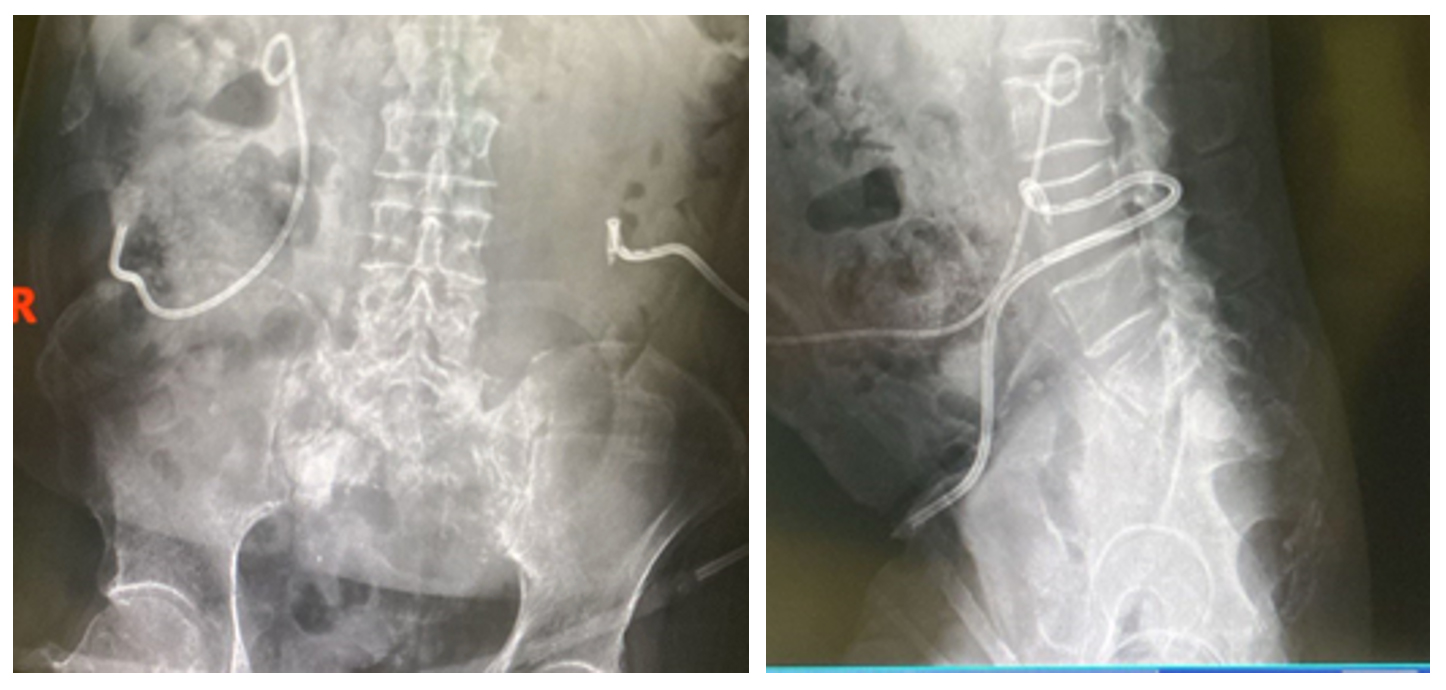

Ameliyat Öncesi: Röntgende nefrestomi kataterleri, sakrumda kemik çimentosu ve harabiyet görülmekte.